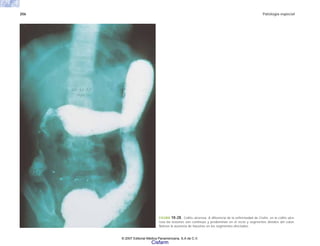

FIGURA 6-31. a) Vasculitis coronaria en un caso de SIDA que muestra necrosis